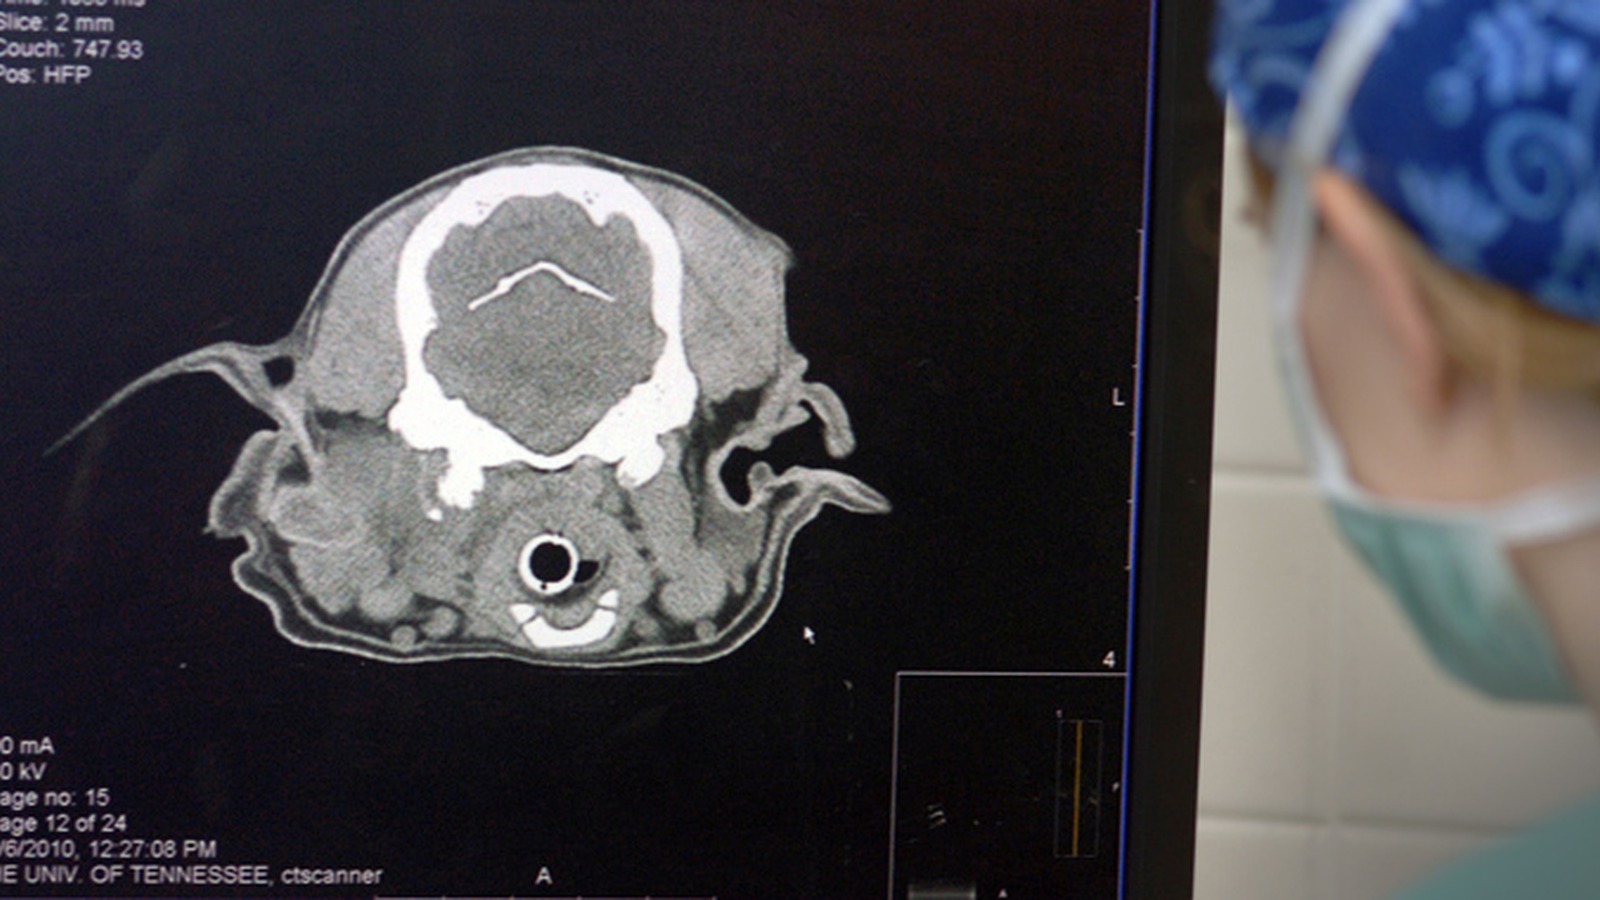

Veterinary Radiologists

Veterinary Neurologists